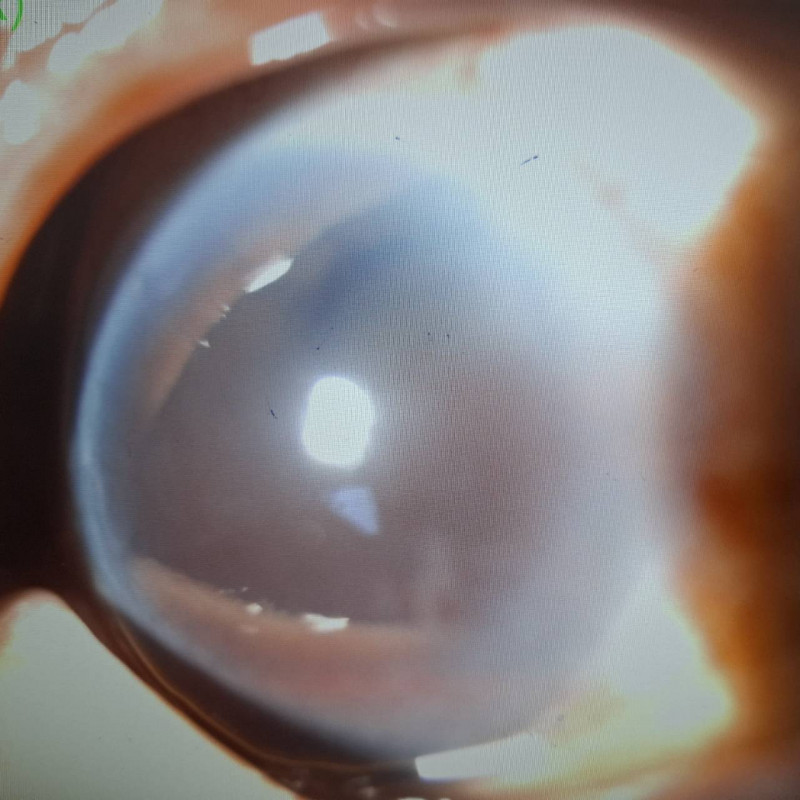

6旬男注射瘦瘦針2個月後,左眼出現1/6前房出血。(醫師洪啟庭提供)

洪啟庭表示,林男過去即因左眼為前增殖期視網膜病變,最佳矯正視力約0.05,在眼科追

蹤治療,這次緊急就醫,經檢查後,發現右眼正常,但左眼左眼眼壓高達35mmHg、視力降

為眼前10公分,同時約有1/6的前房玻璃體出血,病人自述沒有外傷撞擊。術後5天前房又

再度出血,眼壓甚至高達42mmHg,而且出血量越來越多,即使再採最新止血方法仍持續出

血,目前該病患左眼視力僅剩光感,狀況非常不樂觀。